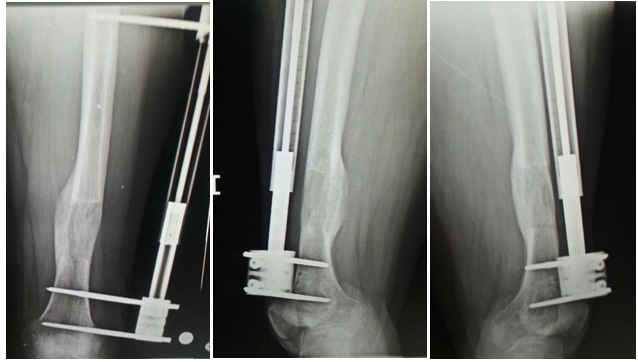

Uzuv uzatma, tıbbi olarak bacak veya kol kemiklerinin kontrollü şekilde uzatılması işlemine verilen addır. Genellikle bacaklarda uygulanır ve ortopedik bir cerrahi prosedürdür.

Bu yöntem, doğuştan kısalık, travmalar sonrası uzuv eşitsizliği ya da sadece estetik amaçlı boy uzatma isteği için tercih edilebilir.

Bu işlem aylarca süren, sabır ve düzenli takip gerektiren bir süreçtir. Uzuv uzatma ameliyatları uzman ortopedistlerce yapılır ve her hasta için uygun olmayabilir. Bu nedenle ciddi bir tıbbi değerlendirme şarttır.